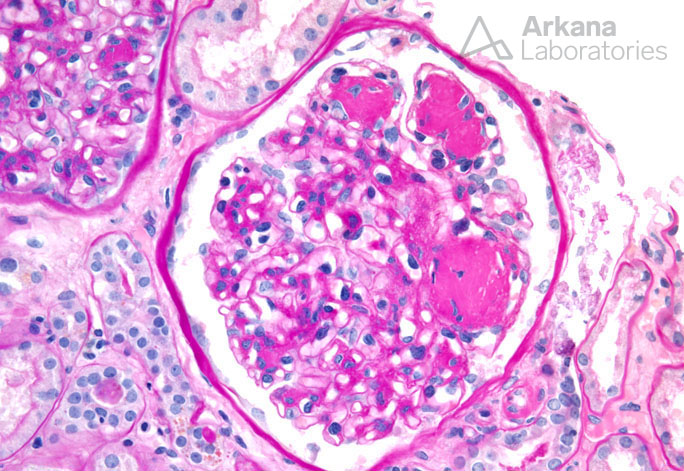

Nodular Glomerulosclerosis PAS